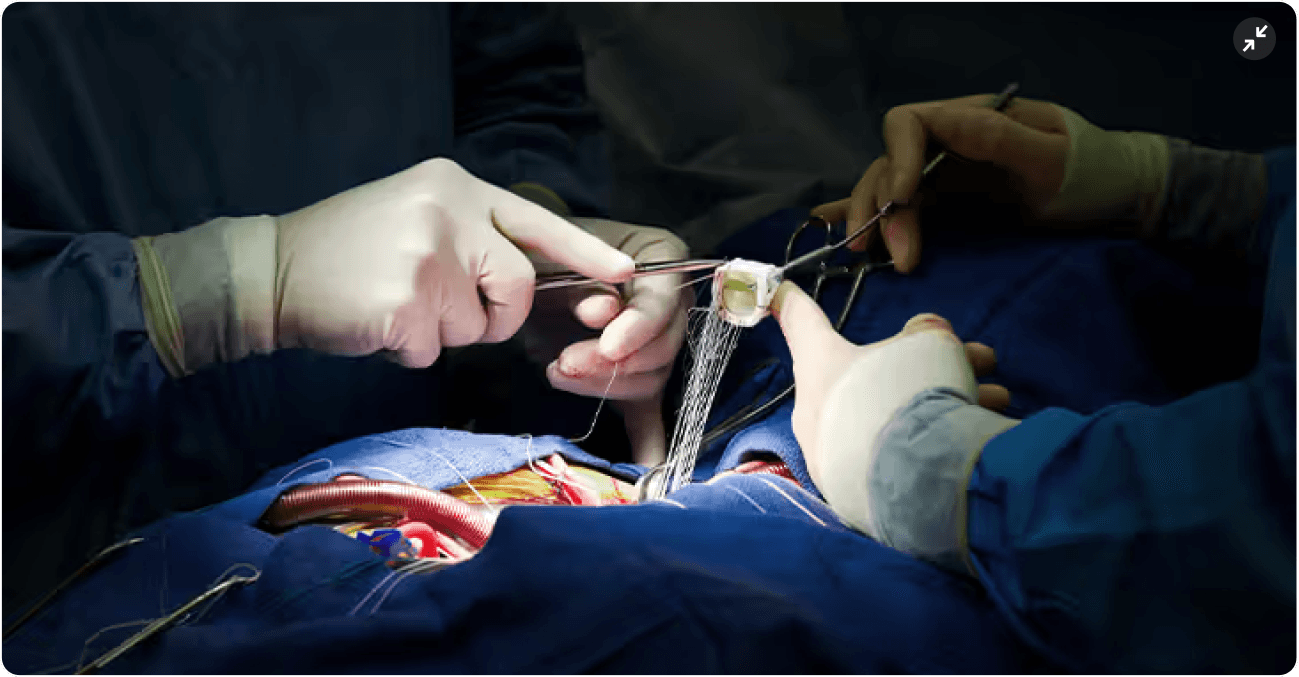

Pre-op

Intra-op

Post-op

Device use

Retractors

Suction

Video Player

Phase

Intraoperative

Event Type / Action

Device Usage

Camera View

Surgeons Site

Instrument Tags

Notes

Time Stamp

Start Time

End Time

Total Time

00:45:00

Attach Screenshot

Annotation

Data

Suction

Retractors

First harpoon device inserted and fired. Maneuvered inside the cavity of patient with one hand (right).

This project is blurred for confidentiality

Designing a surgical recording and annotation platform from the ground up

UX/UI Design